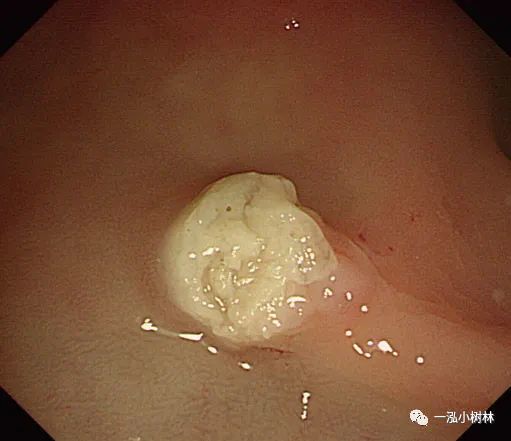

例2 小息肉的冷钳息肉切除术示例

图2a 横结肠3mm大小0-IIa型息肉

图2b 病灶活检钳咬除

图2c 病变是完全被活检钳所钳除

图2d 在同一部位未发现肿瘤残留

2.最近的一项随机研究表明,大小为1~3mm的息肉是冷钳息肉切除术的最佳适应证;可以经1或2次连续活检完全切除。